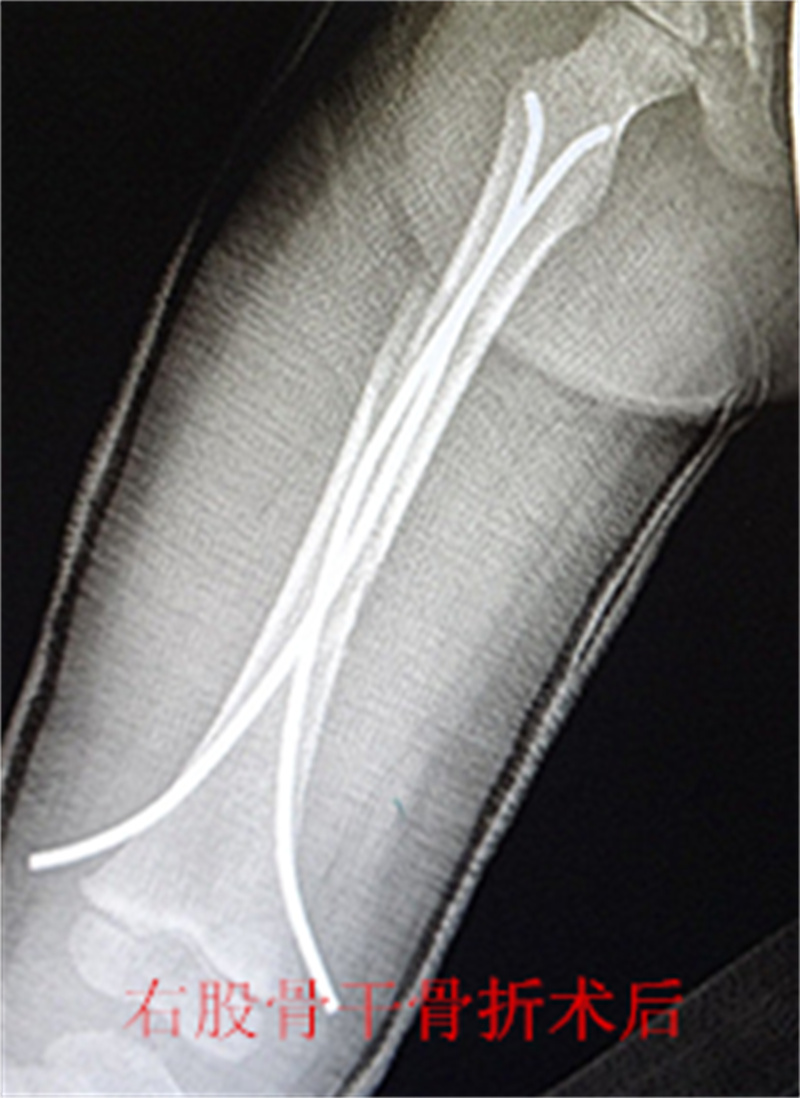

,弹性髓内钉内固定解决了这个矛盾。有人说,弹性髓内钉的出现是上天对儿童的恩惠。的确,弹性髓内钉是治疗小儿长管状骨骨骨折的一种理想、可靠的内固定方法。弹性髓内钉技术发源于法国,在欧洲广泛应用后,现已为全球所接受,被称为是儿童骨科界的一次革命。徐州儿童医院骨一科应用弹性髓内钉技术治疗四肢长管状骨骨折,具有创伤小、恢复快、并发症相对少,孩子能较快恢复正常生活、学习等优点。该技术先将骨折闭合复位,通过微小的切口将特制的弹性髓内钉置入骨髓腔,达到固定骨折的目的。适用于肱骨,股骨,尺桡骨等部位的常见骨折。